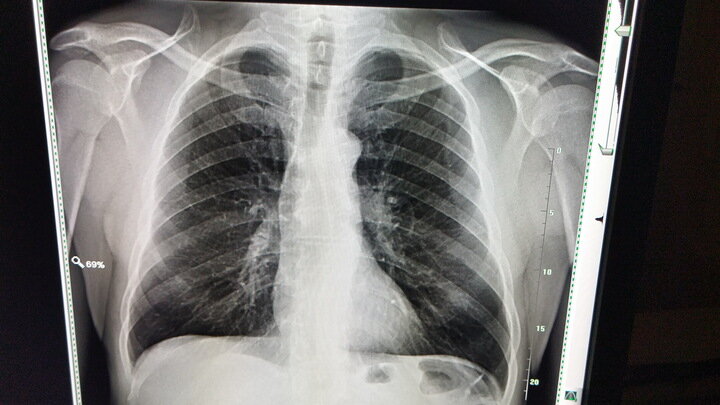

Напомним, чаще всего туберкулез поражает легкие, однако болезнь может задеть и другие органы. Ученые выделяют туберкулез лимфоузлов, пищеварительной, нервной и мочеполовой системы, костей и суставов.

Существуют открытая и закрытая форма туберкулеза. В первом случае больные выделяют инфекцию в окружающую среду и могут заразить окружающих, во втором — нет. Открытую форму лечат только в больничном стационаре до тех пор, пока человек не перестанет представлять опасность для окружающих.